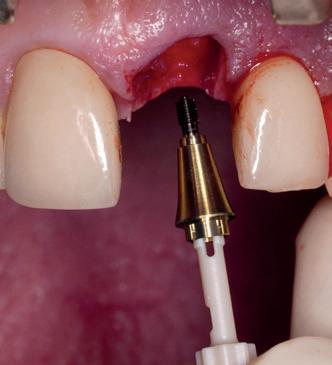

12. Direct post-op. Een direct geplaatste tijdelijke kroon. Vastgezet met een torque van 20 Ncm en gehecht met prolene 5/0.

13. Röntgenfoto ter controle van de pasvorm van de direct geplaatste tijdelijke kroon.